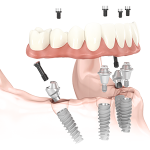

Los implantes dentales son la mejor alternativa para sustituir las piezas dentales perdidas y para el anclaje de las dentaduras. Un implante dental realiza la función de raíz artificial del diente que se ha perdido. La incorporación de las mejores tecnologías a nuestra clínica en el ámbito de la implantología permiten tratamientos con cirugía mínimamente invasiva y guiada por ordenador.

Realizamos la técnica de “carga inmediata”, en la que el paciente puede disfrutar de sus dientes en un solo día con total garantía. En la misma cita hacemos las extracciones de los dientes en mal estado, colocamos los implantes dentales y a las pocas horas, puede disfrutar de sus dientes totalmente fijos.

Con la técnica de “implantes sin cirugía” y tecnología avanzada por ordenador, realizamos un estudio inicial del paciente en 3D con el que podemos colocar los implantes de forma virtual en la posición más correcta. Posteriormente realizamos el tratamiento mediante guías personalizadas (férulas quirúrgicas), disminuyendo considerablemente las molestias postoperatorias ya que el paciente no llevará puntos de sutura y evitando complicaciones y posibles errores.Las principales ventajas son:

En clínica dental Cárabe estamos en permanente formación para dar las mejores alternativas a los casos más difíciles. Somos especialistas en la técnica All-on-four. Una novedosa técnica mediante la cual el paciente se va el mismo día de la intervención con una prótesis fija sobre cuatro implantes disminuyendo el número de intervenciones quirúrgicas y el tiempo de tratamiento. Es un tratamiento muy aceptado por los pacientes edéntulos también por el precio del mismo, ya que es menos costoso que los demás tratamientos indicados para este tipo de pacientes que necesitan una gran rehabilitación.